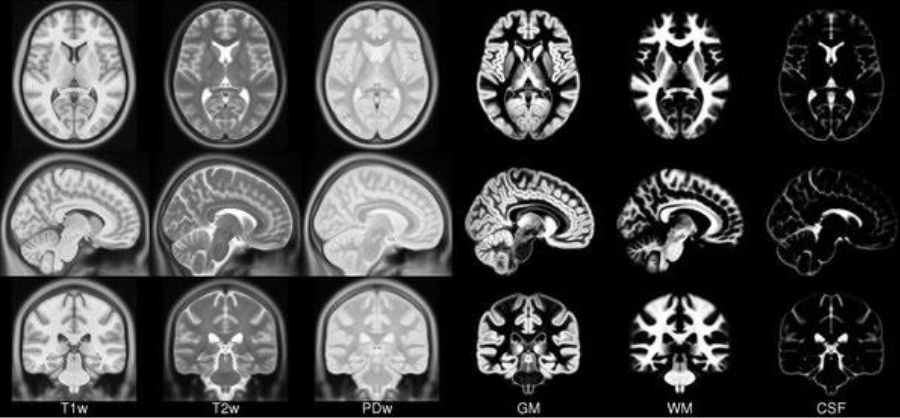

The image registration process consists of combining two images by superimposing one image to the other [47]. In the medical field, image registration allows you to combine data from multiple modalities to obtain comprehensive patient information: it can help monitor tumour growth, facilitate treatment verification, improve interventions, or compare patient data with a template. To apply image registration we need a starting image, a registration algorithm, and a target image, in our case a template. A template is an MRI in a particular spatial location (see Fig. 6 as an example). Model building is an iterative process that involves normalizing, aligning, and averaging an MRI set from different patients [23]. Templates serve as a common reference space and allow researchers to combine and compare data from multiple people and play an important role in a variety of neuroimaging activities:

Through the FLIRT 222https://fsl.fmrib.ox.ac.uk/fsl/fslwiki/FLIRT tool, image registration was applied using the templates available on TemplateFlow [44], as shown in Fig. 7.

Figure 6: Example of templates.